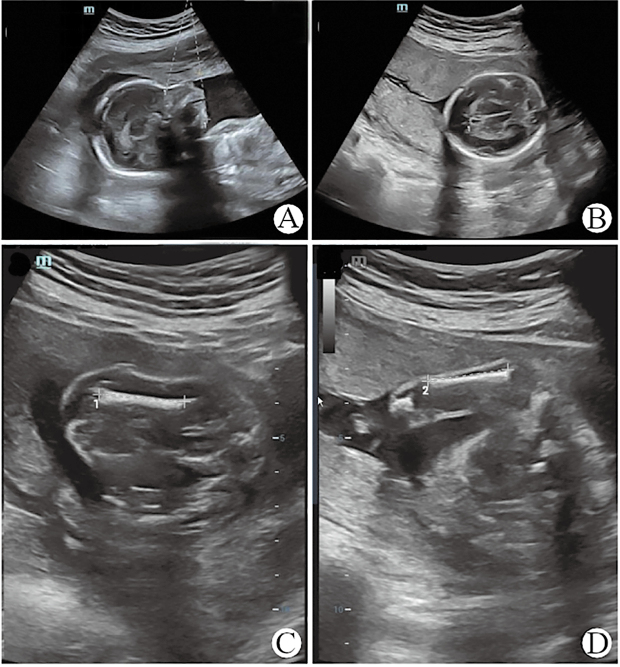

Results: Prenatal systematic ultrasound detected fetal growth restriction. Genetic analysis identified a novel de novo heterozygous variant within the ARCN1 gene-c.1241+5G>A-located in intron 8. In vitro minigene splicing assays demonstrated that the variant led to two abnormal transcripts. The longer transcript retained 189 base pairs of intron 8, resulting in a truncated protein of 414 amino acids (p.Ser415*). The shorter transcript involved exon 8 skippings, producing a truncated protein of 407 amino acids (p.Ile378Serfs*31).

Conclusion: A novel de novo heterozygous variant of the ARCN1 gene, namely NM_001655.5: c.1241+5G>A, was discovered and identified in a fetus with rhizomelic short stature, microretrognathia, and developmental delays.